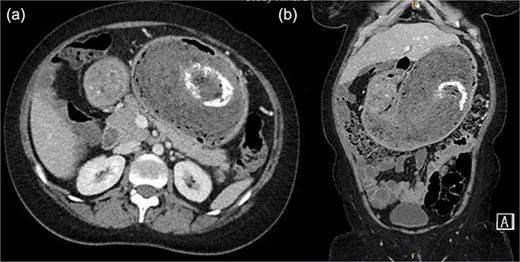

A contrast-enhanced portal venous phase CT scan of the abdomen (Fig. 1a: axial section; Fig. 1b: coronal section) revealed significant gastric distension with a mixed-attenuation intragastric mass showing a whorled pattern and internal calcifications, consistent with a gastric bezoar [2, 4]. An upper gastrointestinal endoscopy confirmed a large trichobezoar occupying ˃90% of the gastric lumen (Fig. 2a and b). The mass was too large and dense for endoscopic removal.

(a) Axial contrast-enhanced CT image of the abdomen showing a markedly distended stomach with a large intraluminal mass displaying a characteristic whorled appearance and internal foci of calcification (arrow), suggestive of a trichobezoar. (b) Coronal CT reconstruction demonstrating the full extent of the bezoar within the gastric lumen (arrow).